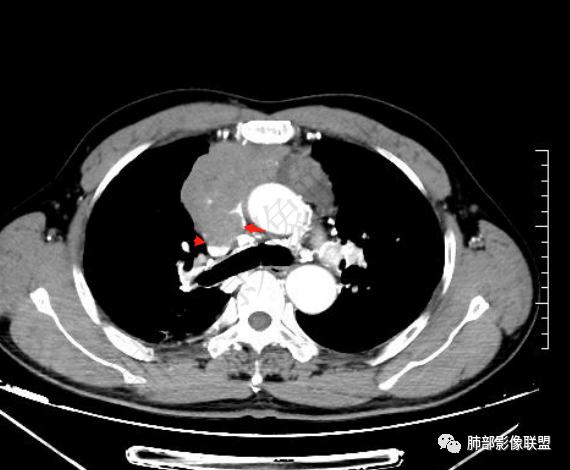

▲上腔静脉内瘤栓

▲病灶骑跨在主动脉前缘,主动脉包绕

2.上纵隔增宽并见不规则块影,密度不均,轻度不均匀强化,隐约见液化密度区。

病灶边界不清,轻度分叶,后方部分紧密包绕升主动脉且侵入上腔静脉及左无名静脉末端,相应上腔静脉及左无名静脉管壁不完整。

晨读病例:男性患者,60岁,面部肿胀一月入院,影像表现,前纵隔实性肿块影,密度均匀,部分层面与腔静脉分界欠清晰,增强扫描病灶轻度强化,病灶内可见低密度无强化区,上腔静脉受侵犯,右侧肺门,纵膈淋巴结增大,考虑恶性病变,胸腺癌>侵袭性胸腺瘤,鉴别淋巴瘤。

晨读:男,60岁,颜面部肿胀1月入院。CT示右肺上叶条索影及实变影伴局部支气管扩张,肺大泡(陈旧性肺结核?)。前纵隔可见实性肿块,骑跨主动脉生长,平扫密度不均匀,内部可见低密度区,增强扫描渐进性不均匀强化,可见坏死区,上腔静脉受侵,考虑为恶性,侵袭性胸腺瘤或胸腺癌>淋巴瘤

晨读:右肺上叶胸膜下实变影伴有肺大泡(结核?),前纵隔一实性肿块,骑跨主动脉生长,病变侵犯压迫腔静脉,平扫密度均匀,增强扫描均匀强化,内部可见低密度小坏死区无强化,考虑:淋巴瘤,鉴别胸腺癌(坏死偏少)